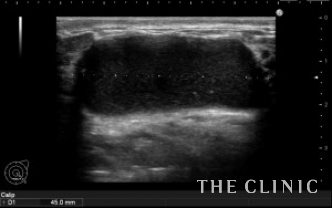

溶解、吸引後です。

黒く見えるヒアルロン酸はなくなりました。

除去したヒアルロン酸です。